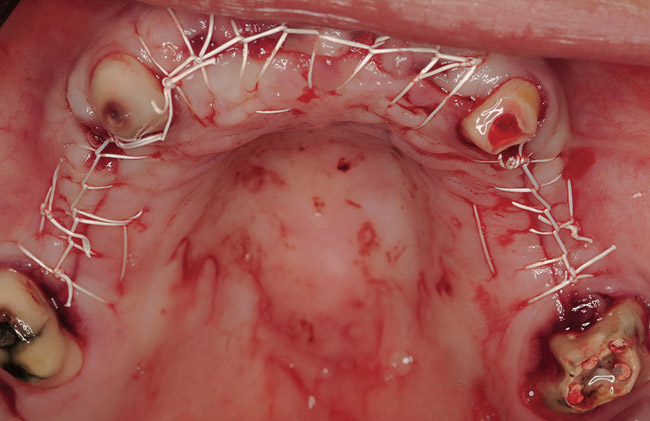

Figure 18  Primary closure was achieved after bilateral sinus grafting and anterior ridge augmentation. The fixed, provisional bridge was then relieved to avoid pressure on the healing sites and recemented.

Figure 18